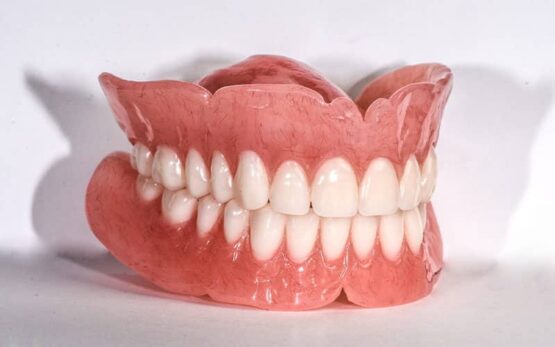

پروتز متحرک دندان مصنوعی است که بیمار میتواند آن را برای تمیز کردن یا خواب خارج کند.

پروتز متحرک دندان مصنوعی است که بیمار میتواند آن را برای تمیز کردن یا خواب خارج کند.

• دست دندان کامل (Full Denture)

پروتز کامل (دندانهای مصنوعی کامل):

در این نوع پروتز، دندانهای مصنوعی کامل در صفحه پایه از مواد پلاستیکی یا کامپوزیت قرار میگیرند. این پروتزها بر روی لثه قرار گرفته و با استفاده از خمیرچسب یا واکس مخصوص به دهان بیمار متصل میشوند.